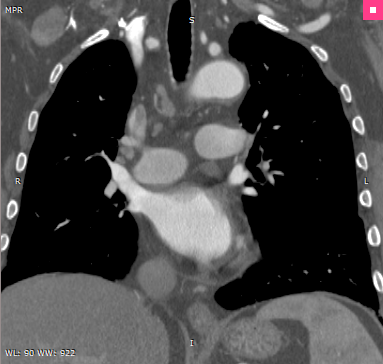

MPR |

MIP |